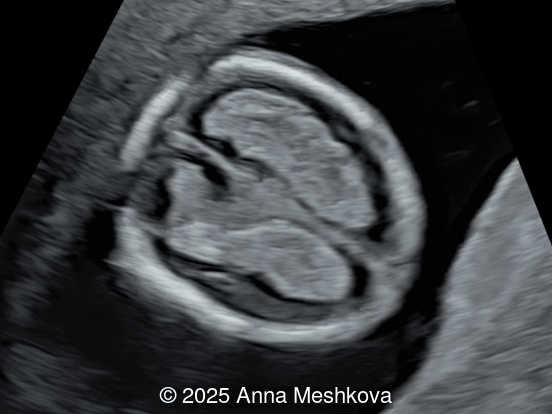

Image 1

• Image 1:  Transverse section of the brain at the level of choroids. Subtle supporting sign of relatively large choroid plexuses and low surrounding cerebrospinal fluid known as the "dry brain" sign.

4.  Dry Brain Sign is characterized by an exaggerated size of the choroid plexuses filling the lateral ventricles due to diminished cerebrospinal fluid in the ventricular system.  Unidirectional leakage of fluid towards the open spinal defect results from a pressure gradient between the “high-pressure” CSF-filled choroid ventricles and, “low-pressure” spinal cord, which produces posterior and caudal displacement of the mesencephalon. As a result, the reduced fluid in the lateral ventricles causes the choroid plexuses to fill the cranial cavity [4-5].

Dry brain sign is demonstrated in the axial view of the fetal head at 13 weeks gestation. Note the large and long choroid plexus in comparison to head size in a fetus with open spina bifida.

Image 10 Dry brain sign is demonstrated in the axial view of the fetal head at 13 weeks gestation. Note the large and long choroid plexus in comparison to head size in a fetus with open spina bifida.